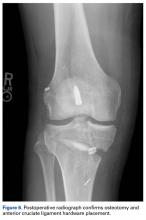

This patient had undergone functional complete medial meniscectomy and had significant medial compartment pain, varus alignment, and minimal medial joint-space narrowing (assumed grossly intact cartilage about plateau and condyle), plus patellofemoral pain and crepitance with a large high-grade posttraumatic patellar chondral lesion with normal patellofemoral alignment. He also had an isolated failed ACL graft from prior ACL reconstruction. The previous hardware placement was analyzed, and it was determined that the femoral interference screw could be left in place and that the tibial interference screw most likely would be removed. The mechanical axis determined from the bilateral long-leg standing images dictated a need for proximal OWMTO for correction up to 8° to allow the axis to cross the center of the knee. The 8° correction is the measured correction needed to move the axis from its pass through the medial compartment to a more balanced position across the middle of the knee.

The overall plan encompassed major concomitant corrective and restorative surgery: tibial osteotomy, medial MAT, revision ACL reconstruction, and fresh mega-patellar OCA. Once the frozen meniscus and eventually the fresh patella (both matched for size) were obtained, arrangements for the patient’s trip for the complex surgery were finalized.